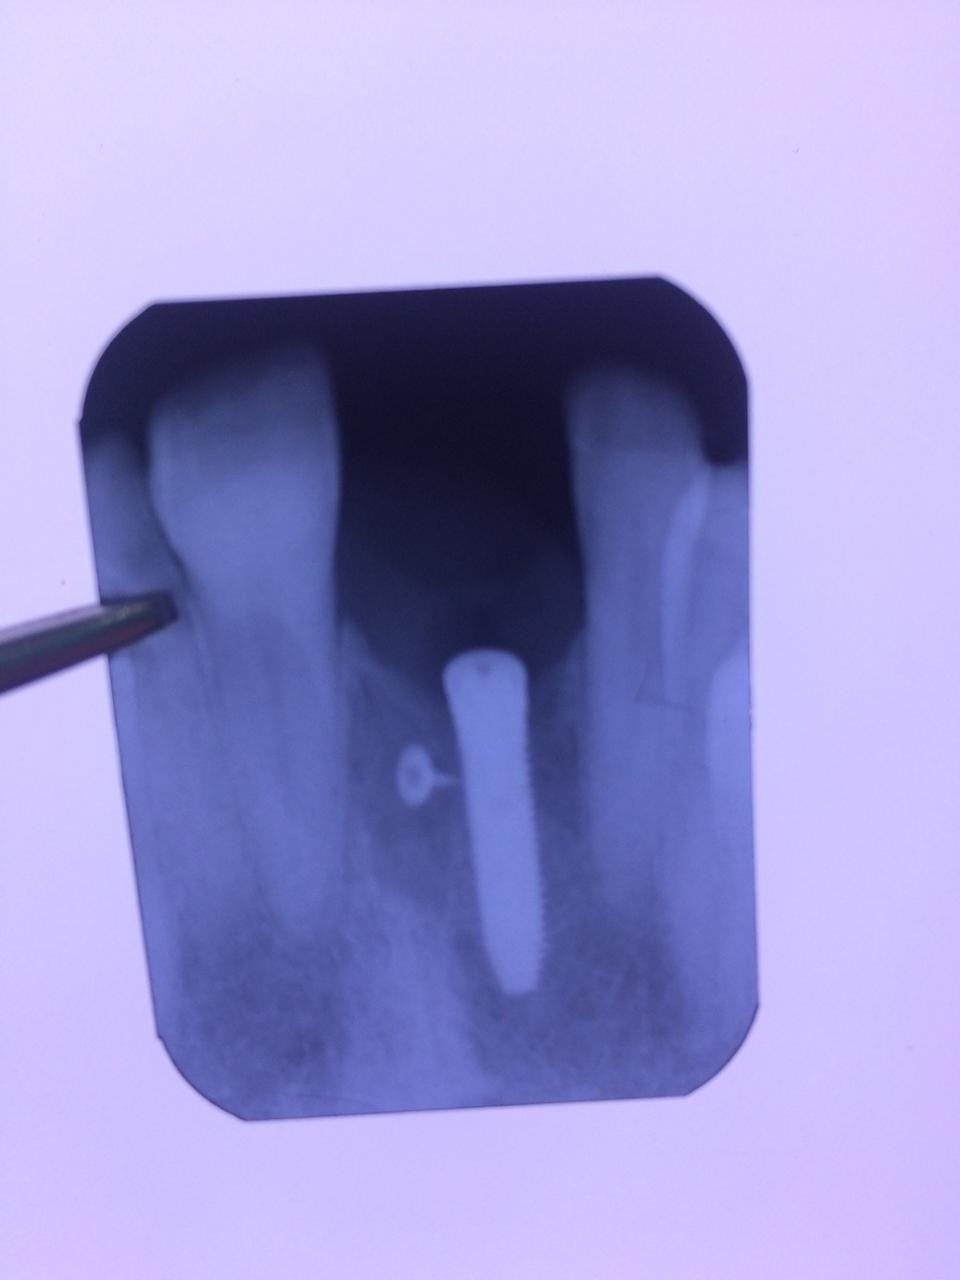

Hola, buenas tardes compañeros. Adjunto radiografía de implante colocado en I-dental en la pieza 12 para ver si me podéis ayudar con la marca para poder rehabilitar. Muchas gracias. Un [...]